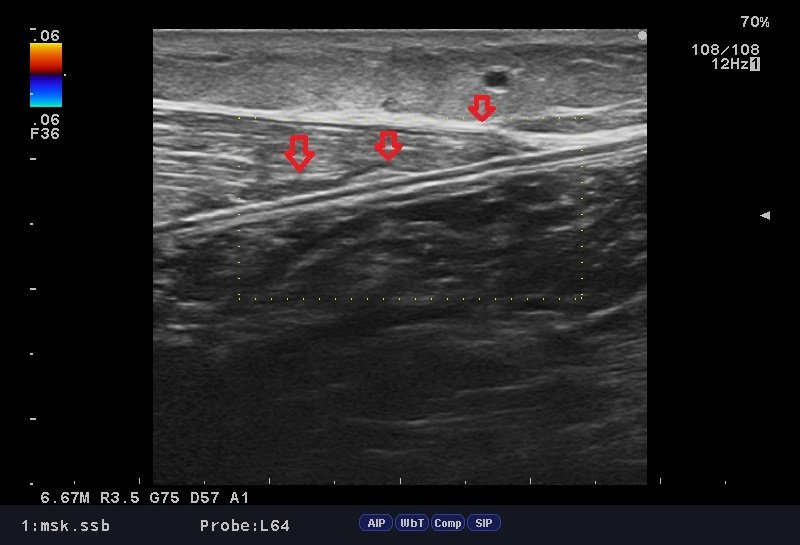

今日の患者さまシリーズは"ふくらはぎ"の肉離れ。

50歳 女性 テニスプレーヤー

テニスのプレー中、ボールを追っかけ蹴り出した時に、左ふくらはぎに衝撃が走り、その後、痛みで動けなくなったと御来院。

来院時、ふくらはぎ 下2/3付近 の内出血、圧痛、運動痛が著明で、「ふくらはぎの肉離れ」の中では筋肉から腱への移行部で高発部位になります。

いつものようにしっかりと問診、視診、触診を行い、確認のためエコー検査。

損傷部位の場所を特定し、治療を行っていきます。